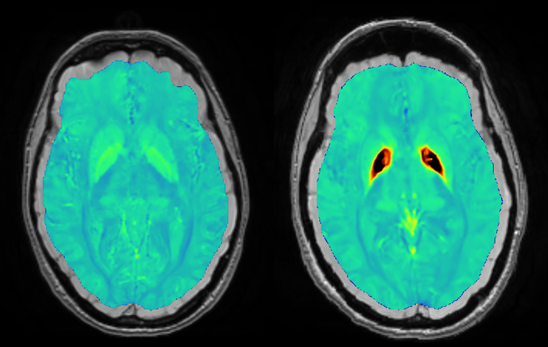

Multiple sclerosis is caused by lesions in the brain and spinal cord that disrupt the functioning of neurons. These lesions are identified by radiologists, who now need to look for specific ‘signatures’. The radiologist looks for the “central vein sign” and the “paramagnetic halo sign”. In this context, iron acts as a marker of the inflammatory process. Hepcidin could play an important role as a peptide that regulates iron accumulation.

Our technology enables these signs to be visualised with great precision and monitored over time.

Visualisation via BIaaS of the new radiological features (McDonald criteria) sought in MS